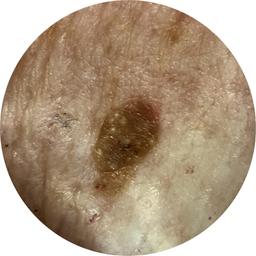

ISIC_8917580

diagnosis_1 Benign

diagnosis_confirm_type single image expert consensus

image_type dermoscopic

lesion_id IL_4139461